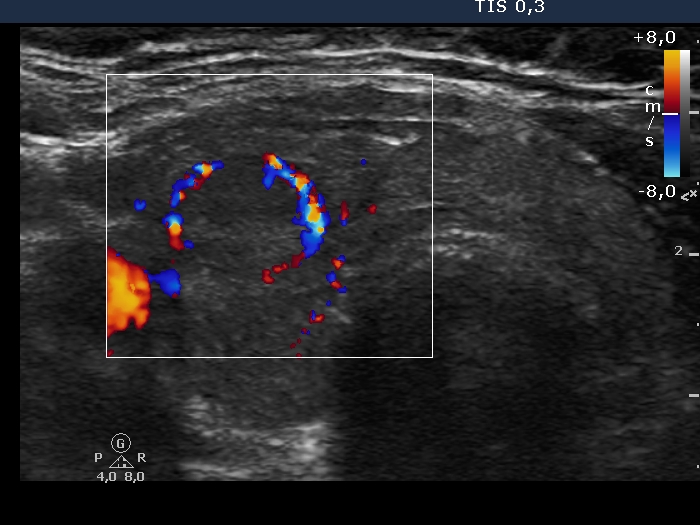

Examination in 2018 (second row of images):

Clinical data. The patient came to a routine follow-up. She had no complaints.

Palpation: unchanged.

Laboratory test: TSH 0.36 mIU/L on daily 125 microgram levothyroxine.

Ultrasonography. Except for the lesion which was previosuly cytologically investigated, the pattern remained unchanged. The lesion in question became cystic and was composed of two chambers. In the tissue part separating the two chambers, hyperechoic granules have appeared. These were mostly related to ventral cystic areas, therefore, they should be regarded as back wall figures.

We recommended that she takes the replacement therapy at the same dose and has a TSH scan after half a year and an ultrasound scan after two years.